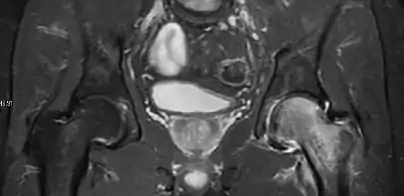

Intra-articular osseous causes of pain include several conditions: avascular necrosis (AVN), transient osteoporosis of the hip (TOH), tumors, and stress or insufficiency fractures. All these entities may present with a pattern of bone marrow edema characterized by decreased signal intensity on T1 weighted images and increased signal intensity on fluid sensitive sequences, such as fat saturated T2-weighted or STIR images. When there is no evidence of a focal lesion associated with the edema pattern, TOH is suspected. When a band of low intensity is seen inside the edematous area, the shape and length of this band become important. It is generally convex to the articular surface in the case of subchondral stress or insufficiency fractures, whereas it is concave, circumscribing all of the necrotic segment, in cases of AVN. When doubts do persist, gadolinium-enhanced MRI tends to show that the proximal portion beyond the band is enhanced in fractures but is not in AVN.[1]

MRI has been shown to have 100% sensitivity and specificity in prospective studies of occult hip fractures. These fractures were diagnosed by bone marrow edema and a low signal fracture line, mainly on T1 or T2 weighted images (Figure 10).[1]

Figure 10:

Stress femoral neck fracture in a young athlete barely visible in X-ray film as a sclerotic line (arrow)[1]

In this case, Tc 99 scintigraphy shows a band of uptake[1]

Furthermore, T1 (left) and DP fat saturated (right) weighted MR images showed the fracture line and a pattern of edema.[1]